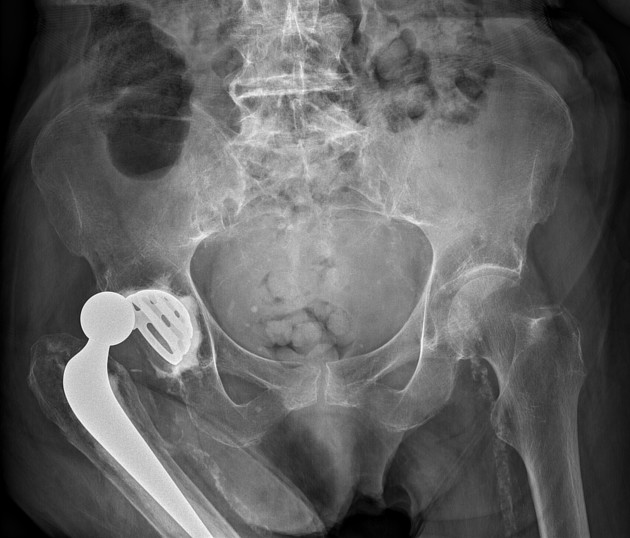

Example 3

Diagnosis

Total Hip Replacement

Image 3: Hacking, C., Qureshi, P. Total hip arthroplasty. Reference article, Radiopaedia.org. https://doi.org/10.53347/rID-37780